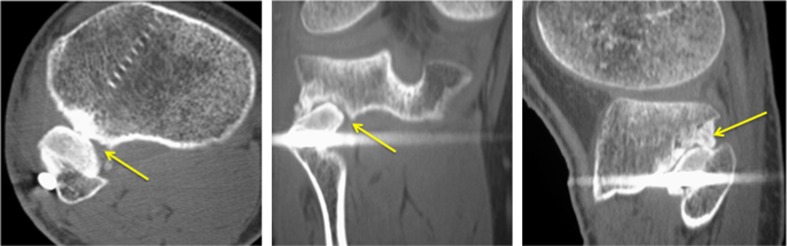

Fig. 3.

(Left to right) axial, coronal, and sagittal CT images, respectively, of the patient in Case 1, demonstrating incomplete fusion at the proximal tibiofibular joint (arrows point to the site of incomplete fusion)